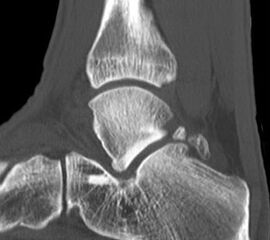

Knochenresektat sowie präoperatives CT (Sagittal- und Transversalebene) und intraoperative Bildwandlerkontrolle im seitlichen Strahlengang nach arthroskopischer Entfernung multipler Ossikel am dorsalen OSG/USG.

Große osteophytäre Anbauten, welche die FHL-Sehne vollständig ummauern, sind ebenfalls sehr gut in der beschriebenen Technik adressierbar. Präoperatives CT und intraoperative Bildwandlerkontrolle im seitlichen Strahlengang (linke Seite).